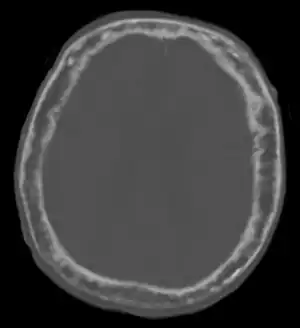

| "This 92 year-old male patient presented for assessment of sudden inability to move half his body. An incidental finding was marked thickening of the calvarium. The diploic space is widened and there are ill-defined sclerotic and lucent areas throughout. The cortex is thickened and irregular. The findings probably correspond to the 'cotton wool spots' seen on plain films in the later stages of Paget’s disease." | |

Paget's disease affecting the skull may cause frontal bossing, increased hat size, and headaches. Often patients may develop loss of hearing in one or both ears[6] due to auditory foramen narrowing and resultant compression of the nerves in the inner ear. Rarely, skull involvement may lead to compression of the nerves that supply the eye, leading to vision loss.[6]

Initially, there is a marked increase in the rate of bone resorption in localized areas, caused by large and numerous osteoclasts. These localized areas of pathological destruction of bone tissue (osteolysis) are seen radiologically as an advancing lytic wedge in long bones or the skull. When this occurs in the skull, it is called osteoporosis circumscripta. The osteolysis is followed by a compensatory increase in bone formation induced by the bone-forming cells, called osteoblasts, that are recruited to the area. This is associated with accelerated deposition of lamellar bone in a disorganized fashion. This intense cellular activity produces a chaotic picture of trabecular bone ("mosaic" pattern), rather than the normal linear lamellar pattern. The resorbed bone is replaced and the marrow spaces are filled by an excess of fibrous connective tissue with a marked increase in blood vessels, causing the bone to become hypervascular. The bone hypercellularity may then diminish, leaving a dense "pagetic bone," also known as burned-out Paget's disease. A later phase of the disease is characterized by the replacement of normal bone marrow with highly vascular fibrous tissue.[26]